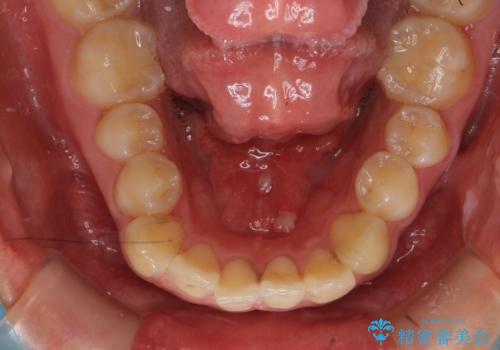

舌が持ち上がらない 舌小帯切除

- 舌小帯の切除を希望して来院。

症例写真を見て他県からお越しになったとのことです。

術後に舌の運動(MFT)を行うことで、退縮の防止になります。

舌を持ち上げた時に、ハート型になるのが適応症です。